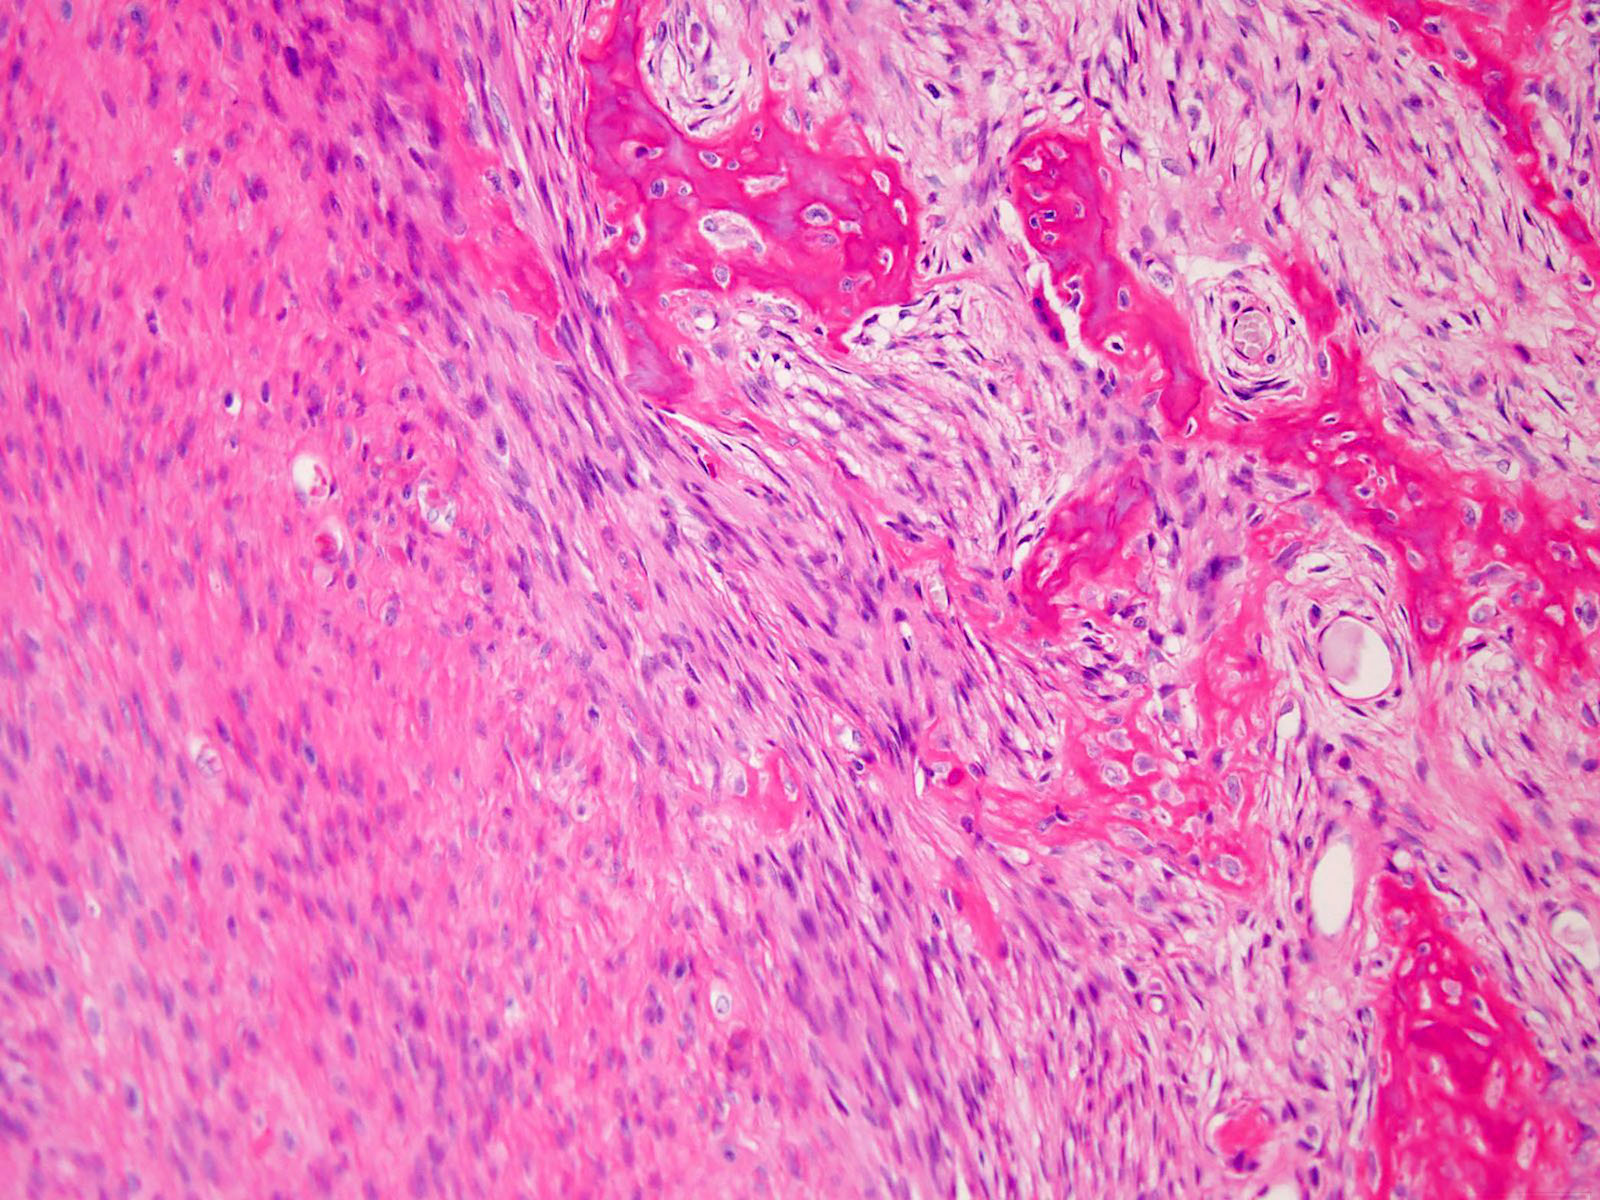

Histological image showing spindleshaped cells with dull nuclei Spindle Cell Osteosarcoma Spindle cell sarcomas of the bone are often found in the arms, legs. What is spindle cell sarcoma? Spindle cell sarcoma is a rare malignant (cancerous) tumour which can develop in the bone or soft tissue. Tumors usually form in your thigh. A spindle cell sarcoma is a soft tissue tumor that originates in a bone. Spindle cell sarcoma is. Spindle Cell Osteosarcoma.

Pathology reports showing spindleshaped cells with irregular nuclei Spindle Cell Osteosarcoma What is spindle cell sarcoma? Spindle cell sarcomas of the bone are often found in the arms, legs. Very rarely malignant mesenchymal tumours that more commonly arise in soft tissues can present as a primary (often spindle cell) sarcoma of bone. Spindle cell sarcoma is a rare bone cancer that most often affects the long bones in your arms and. Spindle Cell Osteosarcoma.

Spindleshaped cells having pleomorphic hyperchromatic nuclei (fi Spindle Cell Osteosarcoma What is spindle cell sarcoma? A spindle cell sarcoma is a soft tissue tumor that originates in a bone. Spindle cell sarcomas of the bone are often found in the arms, legs. Spindle cell sarcoma is a rare bone cancer that most often affects the long bones in your arms and legs. Very rarely malignant mesenchymal tumours that more commonly. Spindle Cell Osteosarcoma.

Microscopic pathology. A spindle cell malignant tumor with local Spindle Cell Osteosarcoma What is spindle cell sarcoma? Spindle cell sarcomas of the bone are often found in the arms, legs. A spindle cell sarcoma is a soft tissue tumor that originates in a bone. Tumors usually form in your thigh. Spindle cell sarcoma is a rare malignant (cancerous) tumour which can develop in the bone or soft tissue. Very rarely malignant mesenchymal. Spindle Cell Osteosarcoma.

(a) Parallel arrangement of bony trabeculae in a bland, hypocellular Spindle Cell Osteosarcoma Tumors usually form in your thigh. Spindle cell sarcoma is a rare malignant (cancerous) tumour which can develop in the bone or soft tissue. What is spindle cell sarcoma? A spindle cell sarcoma is a soft tissue tumor that originates in a bone. Spindle cell sarcomas of the bone are often found in the arms, legs. Very rarely malignant mesenchymal. Spindle Cell Osteosarcoma.